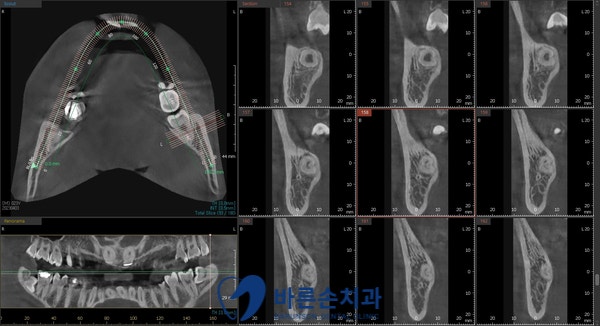

발치전 파노라마와 3D-CT 촬영을 통해

사랑니의 형태와 위치 및

아래턱뼈 하치조신경관의 해부학적 위치를 정확히 확인 후

발치를 진행하게 됩니다